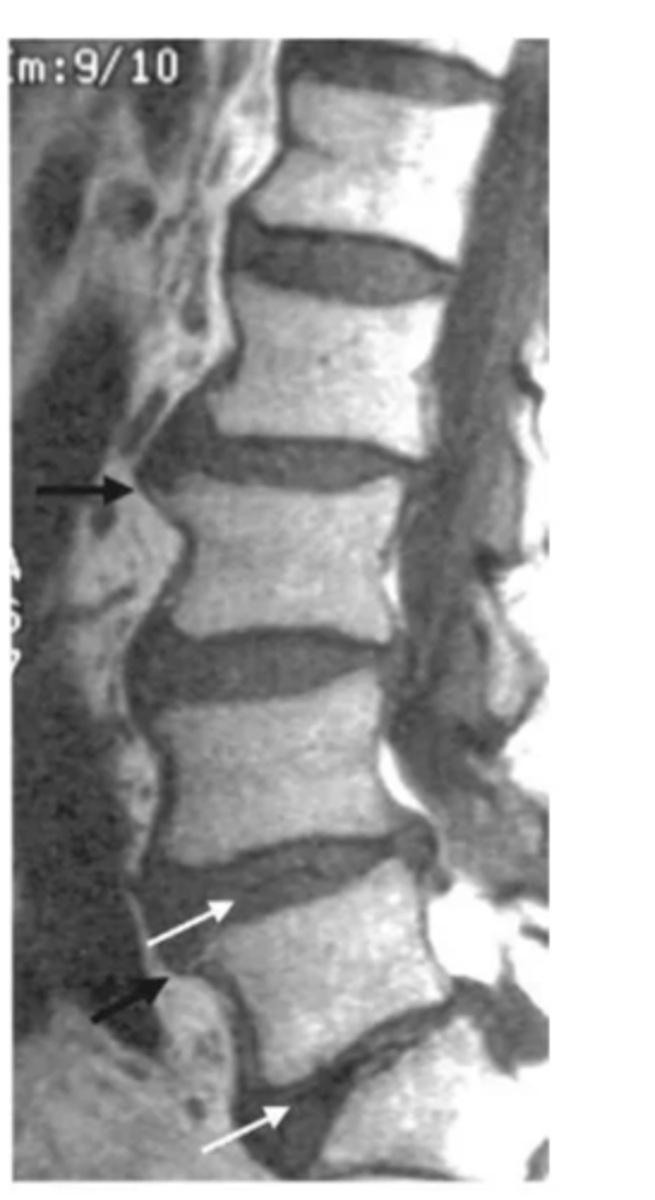

spondylolisthesis

forward slipping of one vertebra over another (caused by vertebral fracture at the pars interarticularis)

spondylolithesis can be caused by ____ or ______

degenerative or traumatic etiology

spondylolisthesis s/s can range from none to _______

severe low back pain with radiculopathy